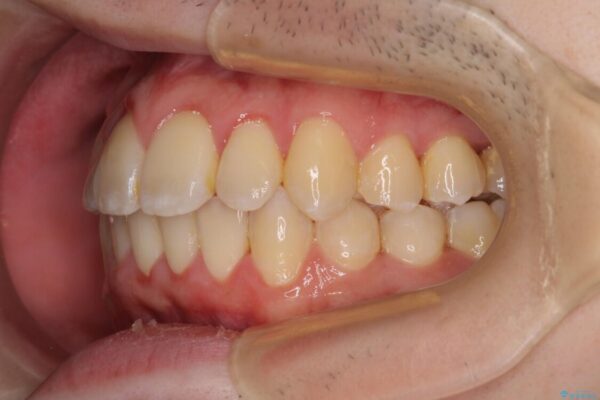

八重歯や奥歯の噛みにくさを気にして来院された患者様です。

前歯のクロスバイトや八重歯の他に、左右最後臼歯のシザーズバイト(鋏状咬合)が認められました。

治療後

• 全顎的なクロスバイト 補助装置を用いてワイヤー矯正 治療後画像